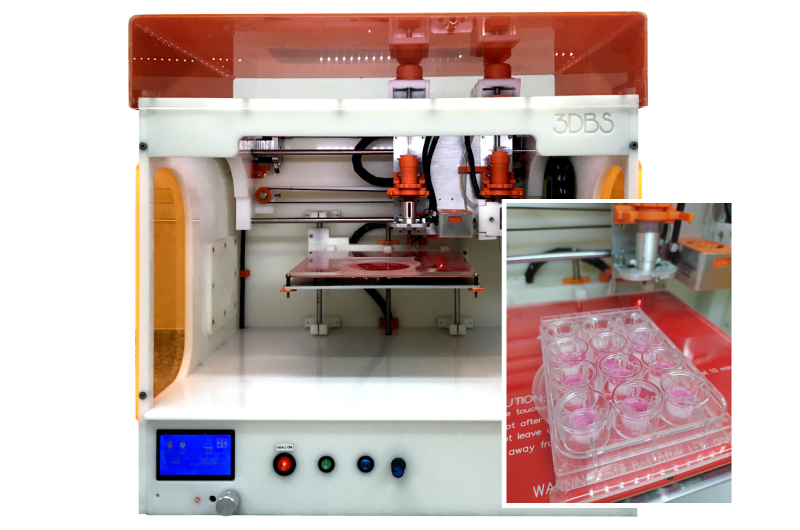

- Basic research in skin physiology and biochemistry

- Drug delivery / drug screening studies

- Skin penetration studies (barrier property)

- Mode of action for pharmaceuticals and assets

- Wound healing studies

- Toxicological evaluation of chemicals